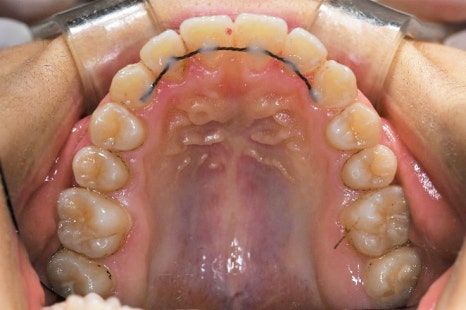

중간단계

브라켓 장치를 붙여서

이를 미세하게 움직여 주는 단계입니다

윗니쪽에는 스프링을 껴서

벌려지려는 탄성을 이용해서

거꾸로 물리는 앞니가

알맞게 자리를 잡을 공간을

만들어주는 것을 알 수 있습니다.

이가 가지런히 펴진 것을 알 수 있습니다.

비발치 치아교정 으로 계획을 수립하게 되면,

이 사이사이를 치간삭제를 하는 방법으로

공간을 확보하며 진행할 수 있습니다.

치간삭제를 해 주면

한 옆면씩 0.3mm를 공간을 얻을 수 있습니다.

여러 이를 적용하면 이에 부담이 낮으며

공간을 많이 확보할 수 있습니다